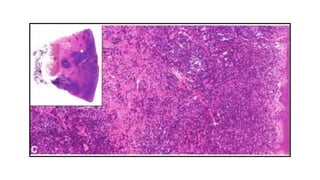

CASE STUDY

9 year old female presented with

• Acute chest pain of few hours

• Difficulty in breathing duration

Systemic examination revealed decreased right sided breath sounds

Other systems revealed no abnormality

There was no history of fever or hemoptysis

Thorough workup revealed no bony or skin lesions

INVESTIGATIONS

Investigation Result

Chest X Ray Multiple pneumatocoeles and right

sided pneumothorax

CT scan Gross distortion of architecture with

multiple thin walled cysts bilaterally

Pulmonary function test Suggestive of both restrictive and

obstructive change

Blood workup for

bacterial and viral

infections

Negative

Bronchoalveolar lavage Unremarkable

Thoracoscopic lung biopsy

S100

CD1a

FINAL DIAGNOSIS

• Pulmonary LCH